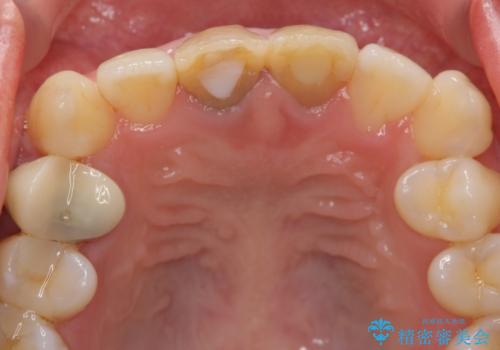

神経をとった前歯が変色してきた

- 昔に神経をとった前歯の変色が気になるとのことでした。

神経の方は問題なさそうだったため、患者様の希望でやりなおさず、土台とセラミック治療を行いました。

歯茎の黒ずみに関しては、中の歯の根が変色して透けている状態のため、変えることは難しいです。